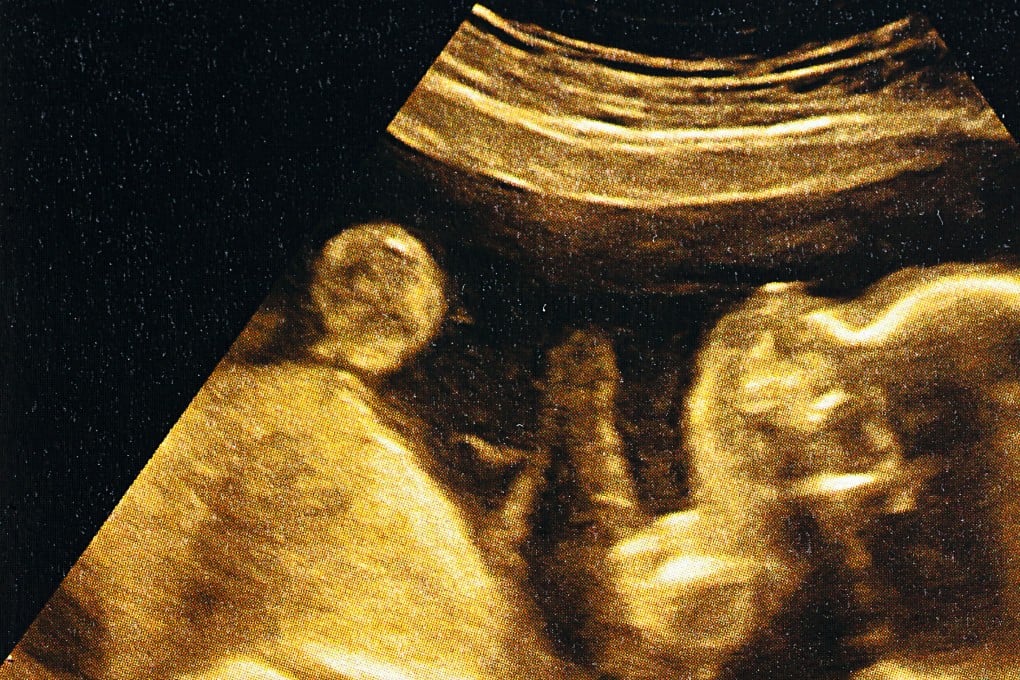

Embryo 3, the fertilised egg that Collins and her husband, Malcolm, had picked, could soon be their daughter – a little girl with, according to their tests, an unusually good chance of avoiding heart disease, cancer, diabetes and schizophrenia.

It’s a new twist on the industry-standard testing known as preimplantation genetic testing, which for decades has checked embryos for rare diseases, such as cystic fibrosis, that are caused by a single gene.

One challenge with leading killers like cancer and heart disease is that they are usually polygenic: linked to many genes with complex interactions. Patients such as Collins can now take tests that assess thousands of DNA data points to decode these complexities and compute the disease risks.